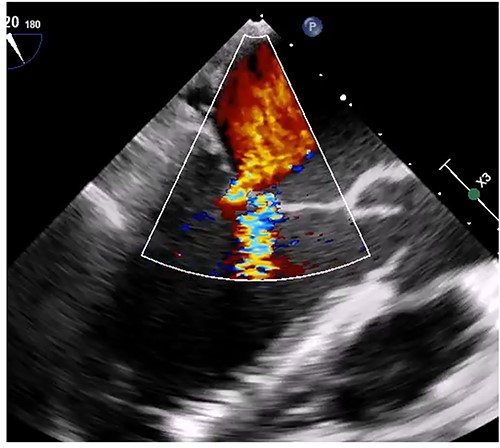

Transthoracic echocardiogram during systole (A) and diastole (B). Giant LA myxoma was prolapsing to the mitral valve orifice.

Median sternotomy was performed, and cardiopulmonary bypass was established via aortic and bicaval cannulation. Under cardiac arrest with antegrade cardioplegia perfusion, the LA was examined via the transseptal approach. The LA cavity was filled with the mass that the stalk was attached to the septal wall at the LA side, and the mass was too big and resected in pieces (Fig. 2). The mitral valve leaflet was intact, and the atrial septum was closed. Dilatated tricuspid annulus was fixed using a flexible band (Tailor Flexible band 29 mm, Abbott). After unclamping of the ascending aorta, a transesophageal echocardiogram points out moderate mitral regurgitation due to mitral annulus dilatation (Fig. 3). Cardiac arrest was performed again, and mitral annuloplasty was performed with a semi-rigid ring (Carpentier-Edwards Physio Ring II 26 mm, Edwards) via left atriotomy. His heart sinus rhythm returned to normal with successful weaning from cardiopulmonary bypass. After the transesophageal echocardiogram procedure, no evidence of the mass and residual mitral regurgitation was confirmed (Fig. 4).